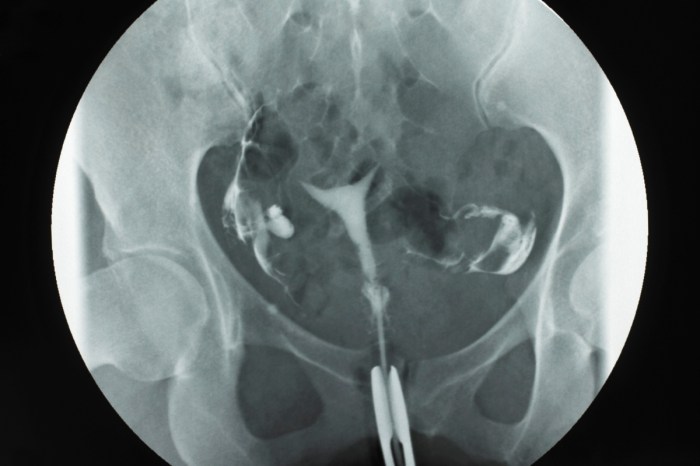

Memahami hasil Histerosalpingografi (HSG) adalah langkah krusial bagi setiap wanita yang sedang berupaya untuk hamil. HSG merupakan prosedur diagnostik yang menggunakan sinar-X untuk melihat kondisi rahim dan saluran tuba falopi. Artikel ini akan memandu Anda melalui dasar-dasar HSG, membantu Anda menafsirkan hasil, dan memahami implikasinya terhadap kesehatan reproduksi Anda.

Histerosalpingografi (HSG) adalah pemeriksaan radiologis yang digunakan untuk menilai bentuk rahim dan memastikan saluran tuba falopi terbuka. Prosedur ini melibatkan penyuntikan cairan kontras ke dalam rahim melalui kateter, kemudian sinar-X diambil untuk melihat bagaimana cairan tersebut mengalir melalui rahim dan tuba falopi. Tujuannya adalah untuk:

Tabel berikut merangkum perbedaan antara hasil HSG normal dan abnormal, beserta penjelasan dan interpretasinya:

| Hasil HSG | Penjelasan Singkat | Interpretasi | Ilustrasi (Deskripsi) |

|---|---|---|---|

| Normal | Rahim berbentuk normal, saluran tuba falopi terbuka, cairan kontras mengalir dengan lancar. | Tidak ada penyumbatan atau kelainan struktural. Kemungkinan hamil normal. | Ilustrasi: Rahim berbentuk segitiga, saluran tuba falopi terlihat jelas dengan cairan kontras yang mengalir hingga ke rongga perut. |

| Oklusi Tuba | Saluran tuba falopi tersumbat, cairan kontras tidak dapat mengalir. | Kemungkinan infertilitas karena sel telur tidak dapat bertemu sperma. | Ilustrasi: Saluran tuba falopi terlihat terputus atau tidak terisi cairan kontras. |

| Hidrosalping | Saluran tuba falopi membesar dan berisi cairan. | Kemungkinan kerusakan tuba falopi akibat infeksi atau peradangan. | Ilustrasi: Tuba falopi terlihat membesar dan berbentuk seperti sosis. |

| Kelainan Rahim | Adanya polip, mioma, atau kelainan bentuk rahim. | Dapat mengganggu implantasi embrio atau menyebabkan keguguran. | Ilustrasi: Gambaran tidak rata pada dinding rahim, atau adanya massa yang menonjol ke dalam rongga rahim. |

Contoh: “Cavum uteri bentuk normal, tampak bayangan filling defect di fundus uteri, kedua tuba falopi paten.”

- Cavum uteri bentuk normal: Bentuk rahim normal.

- Tampak bayangan filling defect di fundus uteri: Ada kemungkinan polip atau mioma di bagian atas rahim.

- Kedua tuba falopi paten: Kedua saluran tuba falopi terbuka.